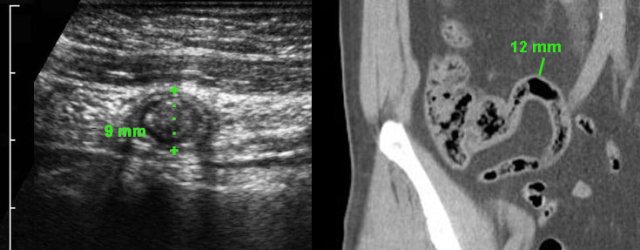

Patient with a small appendiceal abscess, ventrally walled-off by the ileum.

The appendix (arrows) is small because it has evacuated its purulent contents in to the abscess.

Note the calcified fecolith (arrowhead) on the bottom of the abscess.

Drainage was performed from laterally.

Man of 70 years, with a large abscess in the RLQ.

On CT the appendix could not be identified.

US confirms an inflamed appendix (arrow).